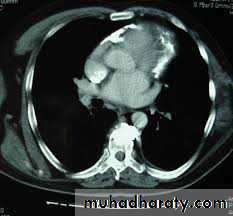

-Echo free zone surround the heart

-CXR- cardiomegaly

Free zone surround heartRT atrial and ventricular collapse

CXR- small heart -Calcification

CT scan,MRI – pericardial thickness /calcification